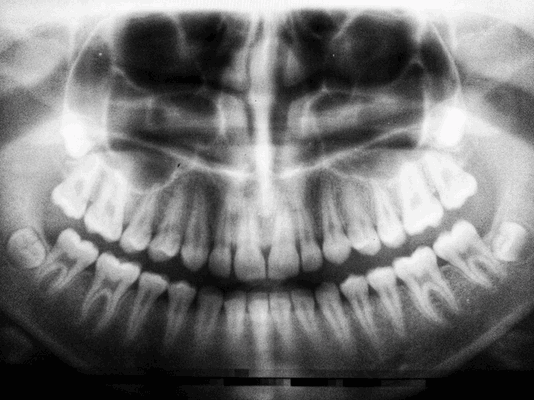

Проводят тесты на жизнеспособность пульпы и оценивают подвижность зубов, выполняют прицельные рентгенограммы.

Проводится с целью выявить состояние костной ткани и зубных корней, исключить противопоказания. Если вы лечите один зуб, будет достаточно прицельного снимка (рентген). Если врачу необходимо увидеть картину целиком, нужен обзорный снимок (ортопантомограмма). Перед имплантацией вас направят на компьютерную томографию.